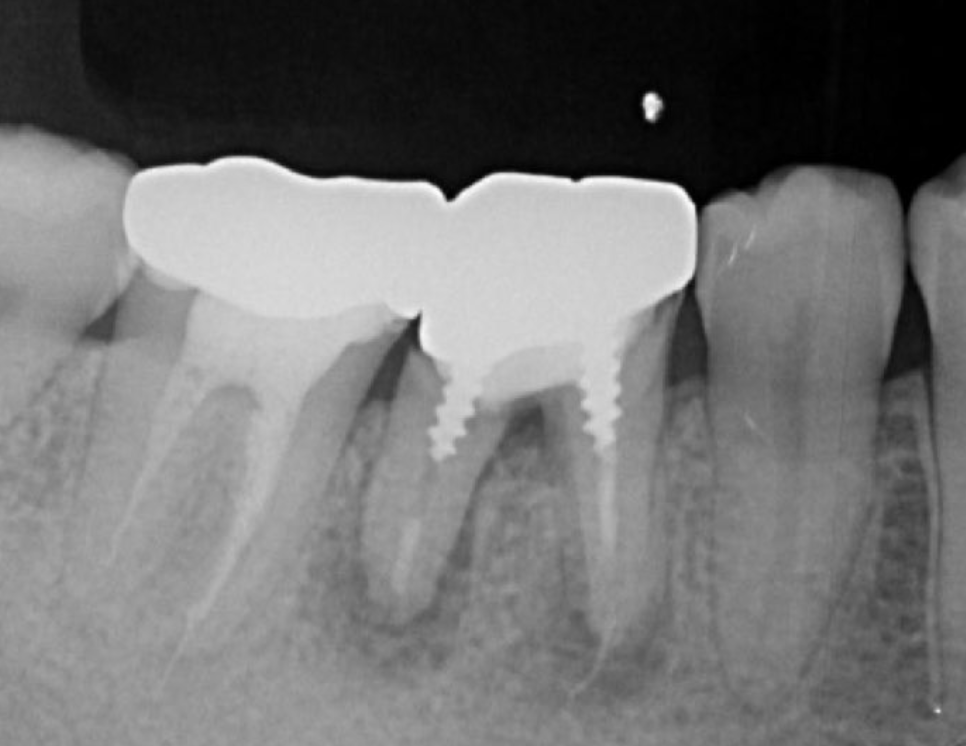

Figure 2.Pre-treatment X-ray findings. A cystic lesion was found in the mesial and distal roots apex, and root nodule of #46.